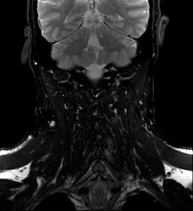

Prueba diagnóstica no invasiva que consiste en la obtención de imágenes de alta definición anatómica del cuello mediante el empleo de un campo electromagnético y ondas de radio (con un emisor y un receptor). No utiliza radiación ionizante. Indicaciones: sospecha de tumor, infecciones, ganglios. - Angio-RM intracraneal

Prueba diagnóstica no invasiva que consiste en la obtención de imágenes de alta definición anatómica de las arterias carótidas y vertebrales a nivel de cuello, mediante el empleo de un campo electromagnético y ondas de radio (con un emisor y un receptor). No utiliza radiación ionizante. En la mayoría de los casos es necesario el empleo de contraste paramagnético (Gadolinio). Permite un estudio angiográfico no invasivo gracias a la inyección de Gadolinio con posterior reconstrucción en 2D y 3D, gracias a estaciones de trabajo especializadas. Indicaciones: problemas circulatorios cerebrales, síncope. - RM Espectroscopia Cerebral

Prova diagnòstica no invasiva que consisteix en l'obtenció d'imatges d'alta definició anatòmica de les artèries caròtides i vertebrals a nivell de coll mitjançant l'ús d'un camp electromagnètic i ones de ràdio (amb un emissor i un receptor). No utilitza radiació ionitzant. En la majoria dels casos és necessari l'ús de contrast paramagnètic (Gadolini). Permet un estudi angiogràfic no invasiu gràcies a la injecció de Gadolini amb posterior reconstrucció en 2D i 3D, gràcies a estacions de treball especialitzades. Indicacions: problemes circulatoris cerebrals i síncope. - Angio-RM d'Aorta Toràcica